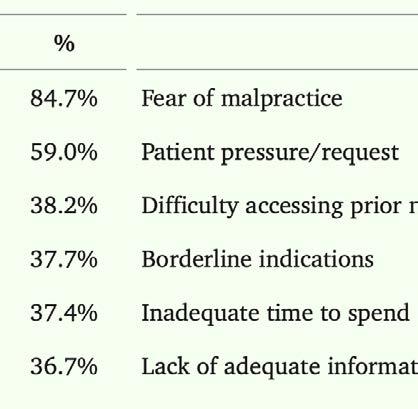

As much as 30% of all medical care is unnecessary, physicians identify fear of malpractice lawsuits as the leading reason. EpiPen funds allergy awareness groups and food allergies are likely overdiagnosed to avoid the risk of missing them.

“Overtreatment in the United States” — Heather Lyu et al., 2017